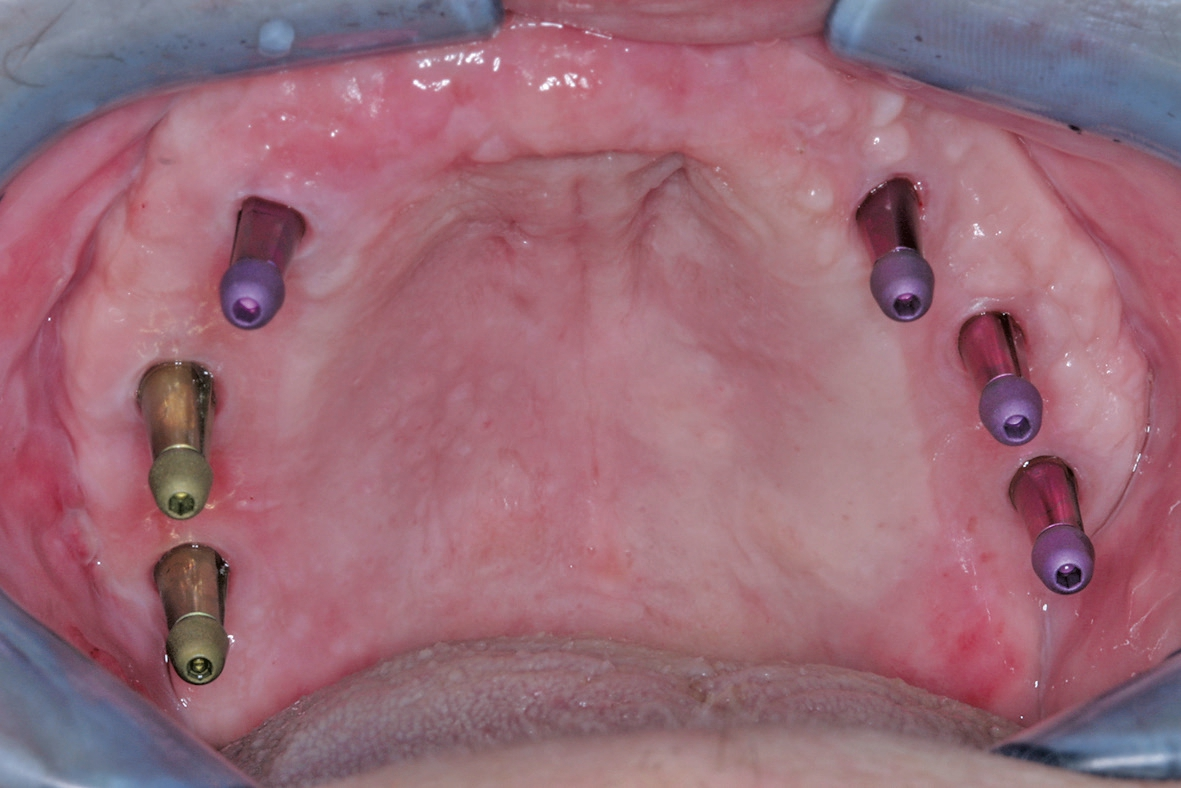

Vor dem zweiten OP-Eingriff nach 4 Monaten wurde im Labor eine Bohrschablone hergestellt. Zudem wurde ein DVT angefertigt, um im Sinne eines backward planning die idealen Implantatpositionen zu ermitteln. Bei Eröffnung des augmentierten Kieferbereiches zeigte sich eine gute Regeneration und Revaskularisierung des Knochens. Sechs Implantate konnten mit ausreichender Länge und passendem Durchmesser so in den augmentierten Bereich (Astratech EV®, Dentsply Sirona Implants, Mannheim) inseriert werden, dass sich eine gleichmäßige Pfeilerverteilung ergab (Abb. 7 u. 8).

Den dritten und letzten chirurgischen Behandlungsschritt stellte die Freilegung der Implantate und Versorgung mit Gingivaformern dar (Abb. 9–11). In diesem Fall wurde ein apikaler Verschiebelappen [5] präpariert, um den ursprünglichen anatomischen Verlauf der mukogingivalen Grenze wieder herzustellen und einstrahlende Bänder im periimplantären Bereich zu vermeiden.